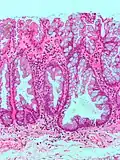

| Tubular Adenoma (Villous, Tubulovillous) | Colorectal | Tubular glands with elongated nuclei (at least low-grade atypia) | Yes | ![]() |

|